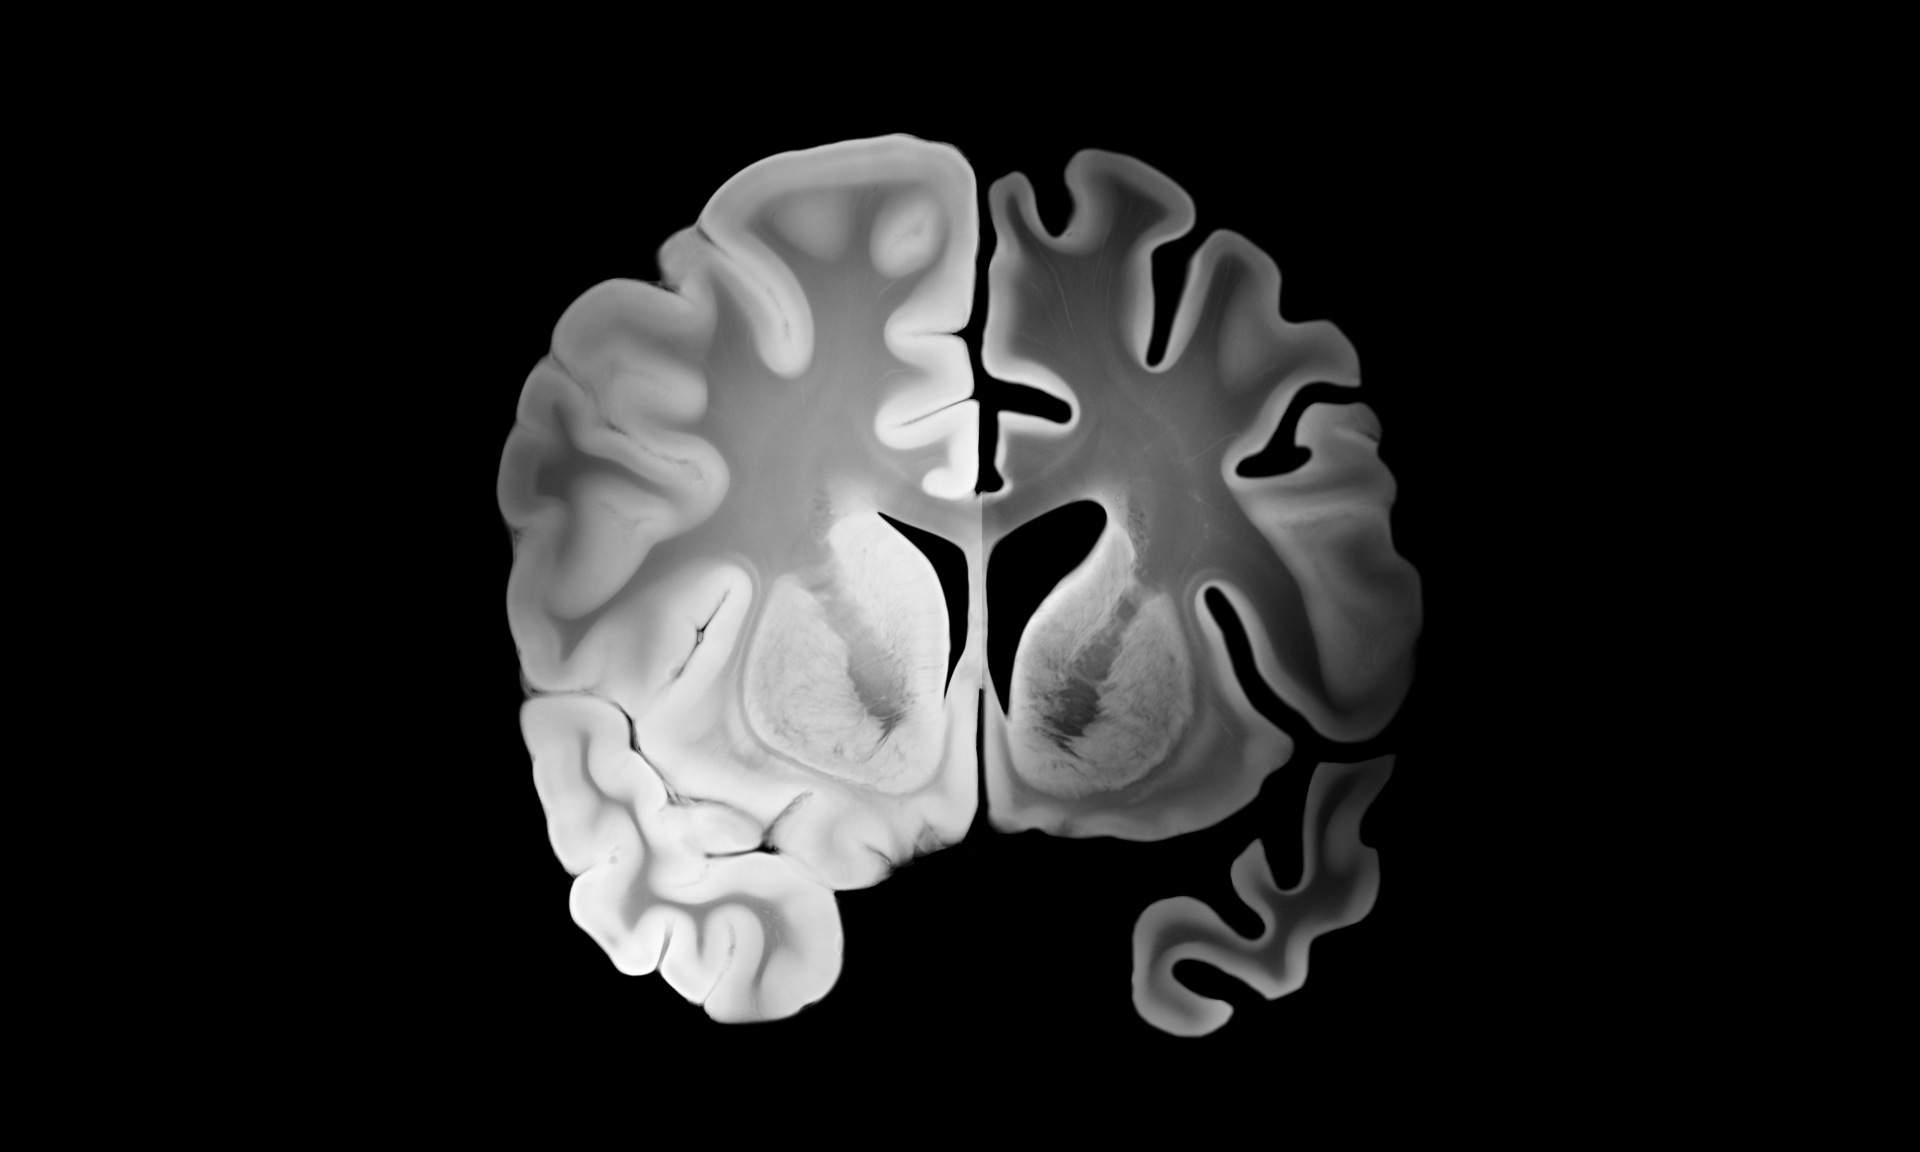

• neurocognitive injury (hippocampal and cortical vulnerability)

The hippocampus is highly sensitive to oxidative stress. When sleep fragmentation increases NADPH oxidase activity in cortical and hippocampal tissue, spatial learning and memory performance deteriorate—reflecting a biochemical injury pattern, not simply “being tired.”